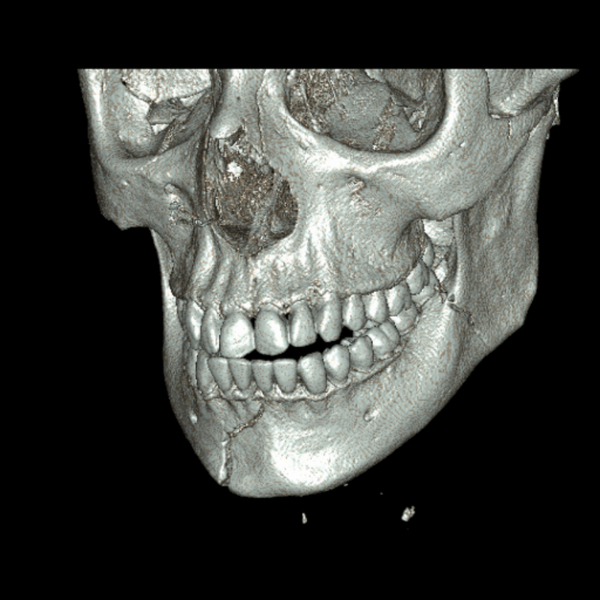

Facial Fracture X-Rays